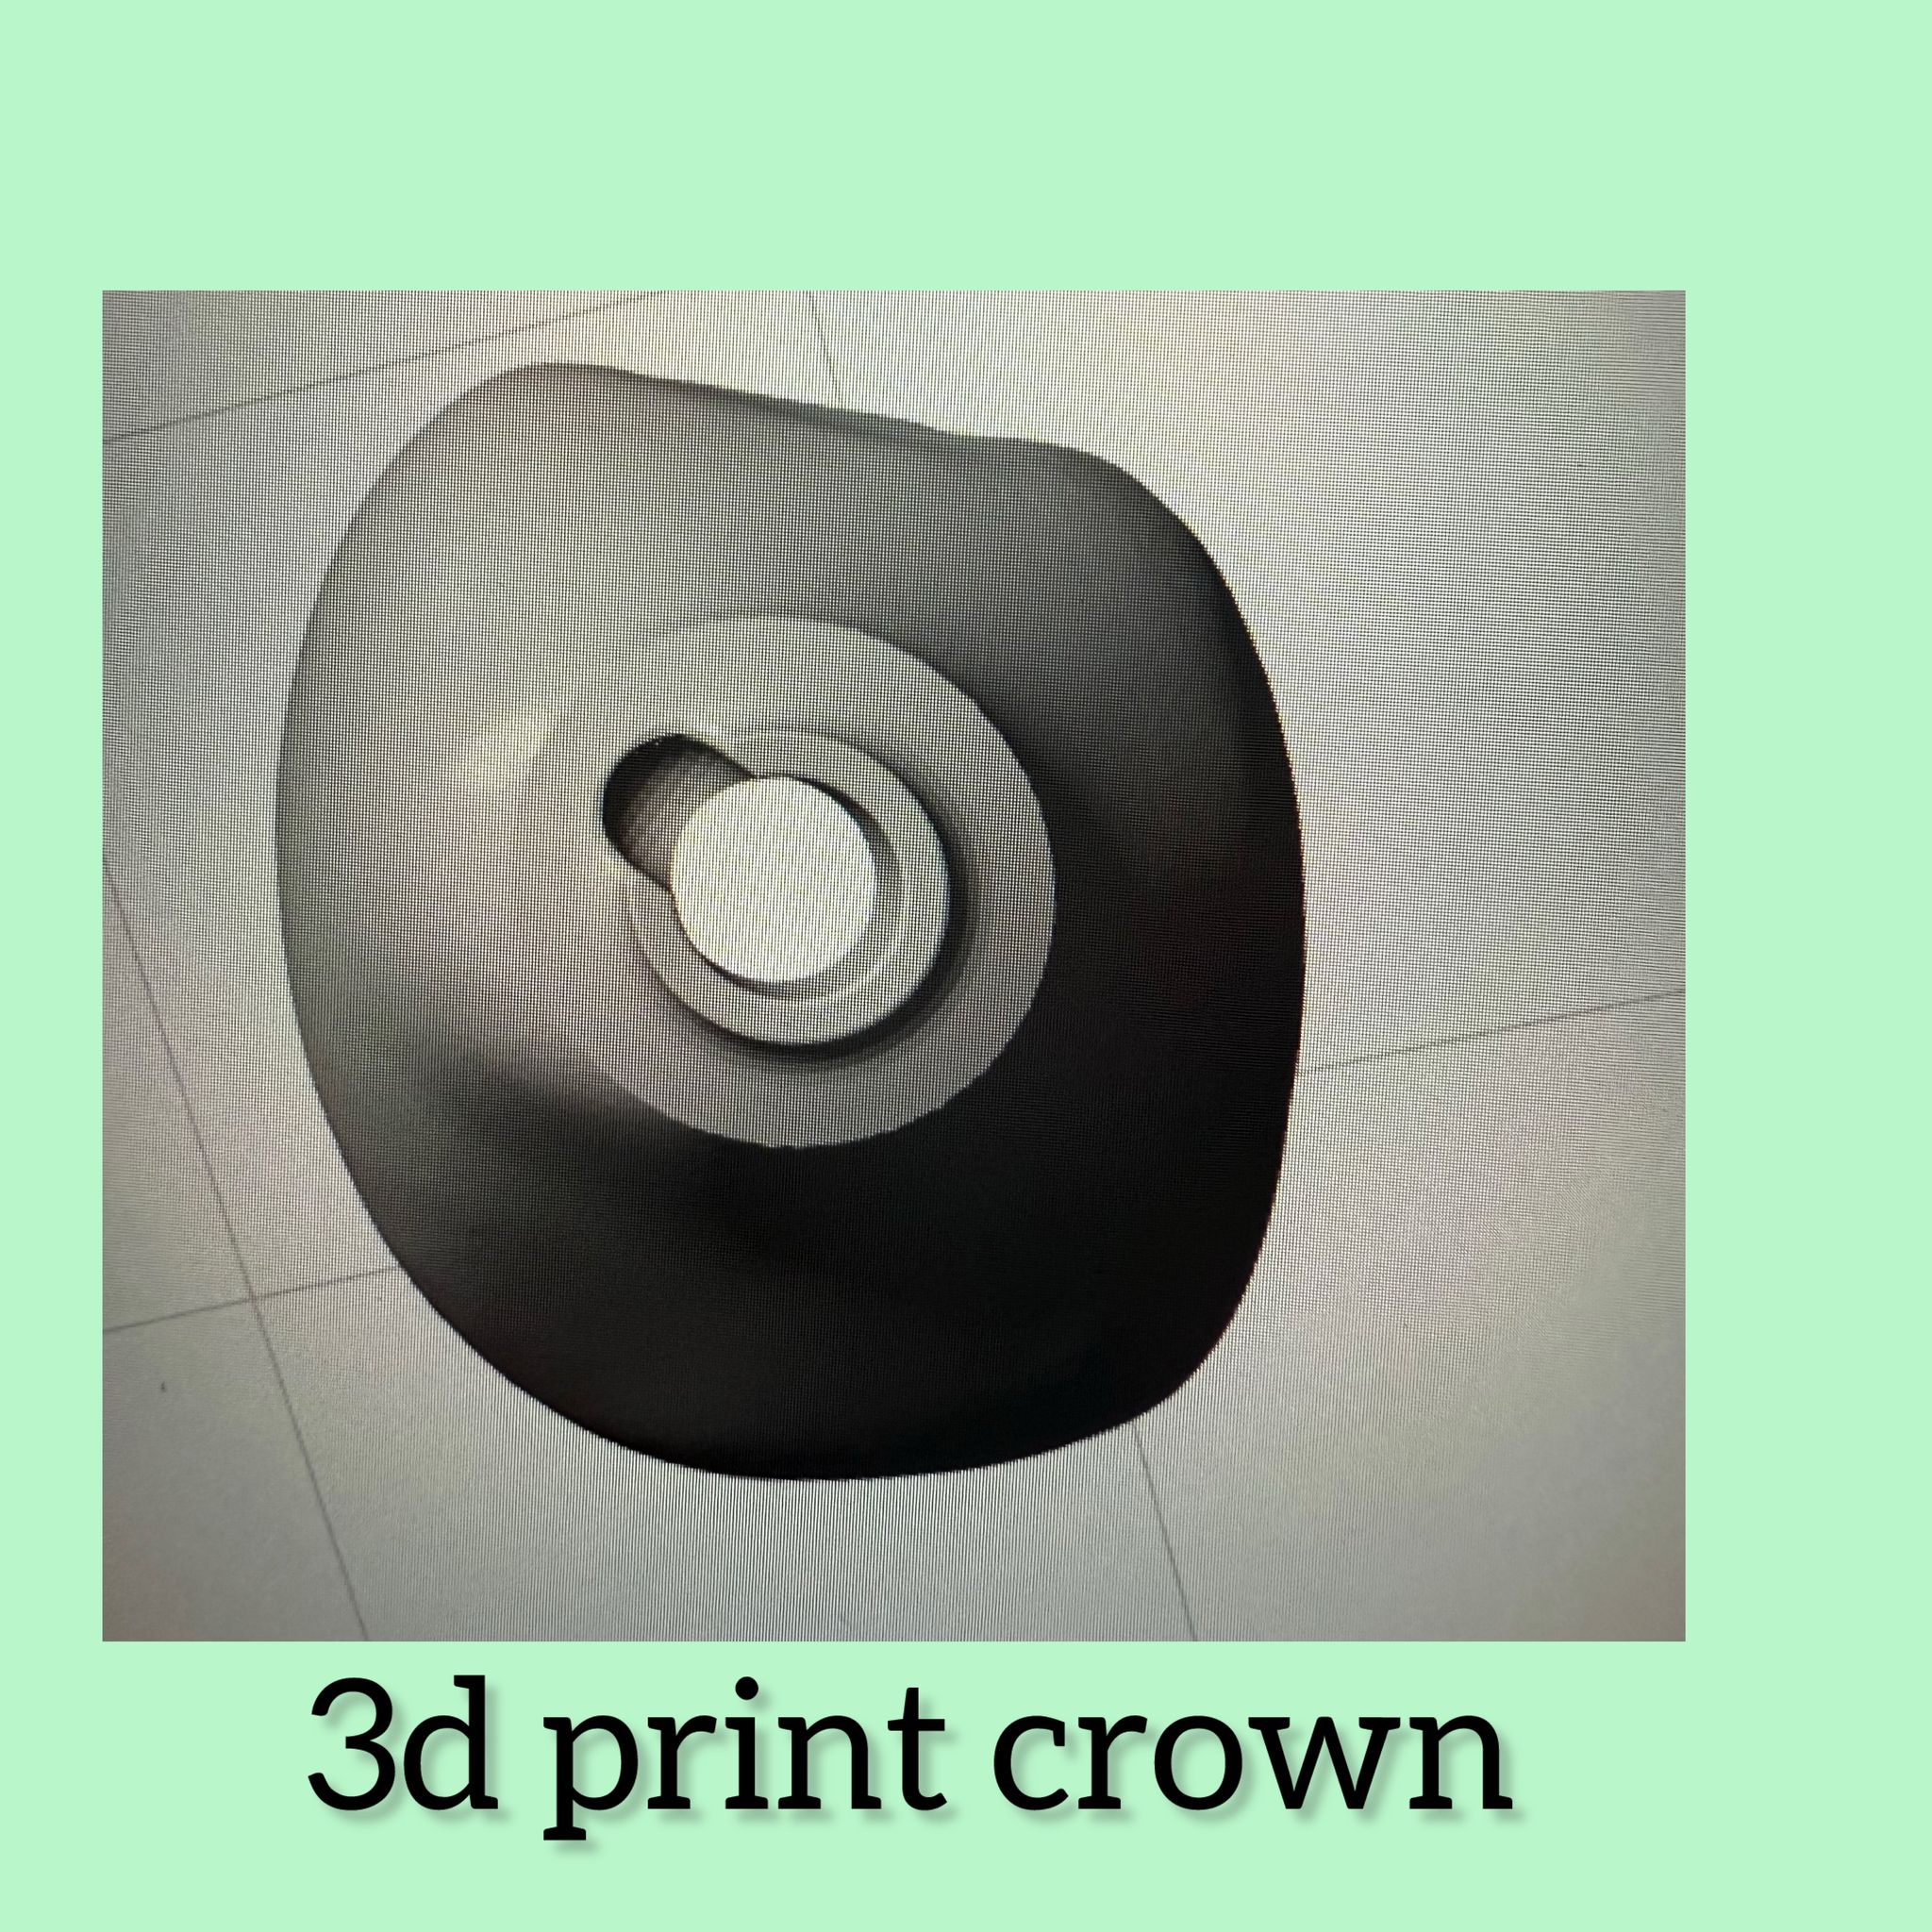

Dental Laboratorium in Amsterdam

Dental Laboratorium in Amsterdam